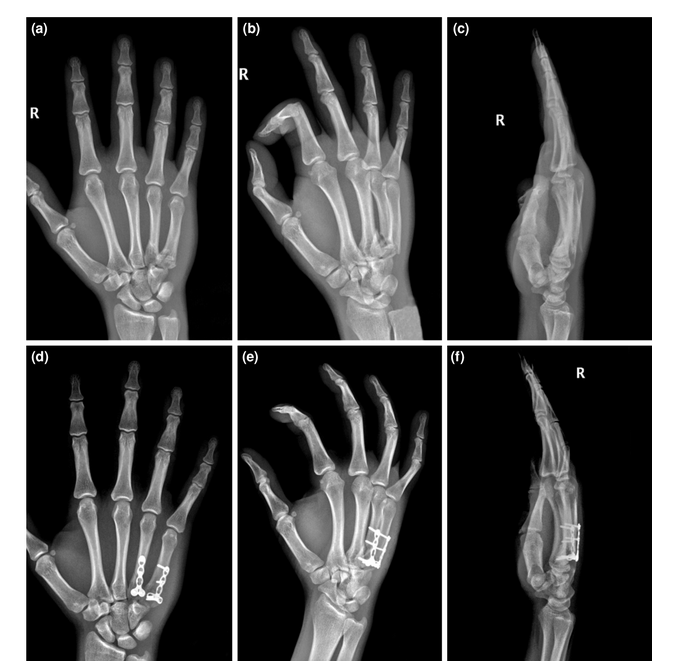

手术患者术前和术后的x线图像。(a)掌骨级联线AP x线。这些线沿着掌骨的轴线画;绿色表示解剖性,红色表示脱位,因为它不与其他关节相交。(b)术前斜位x线片。

手术治疗患者的术前和术后影像;钢板固定的一个例子。(a-c)术前AP、斜位和侧位x线图像。(d-f)术后AP、斜位和侧位x线图像。